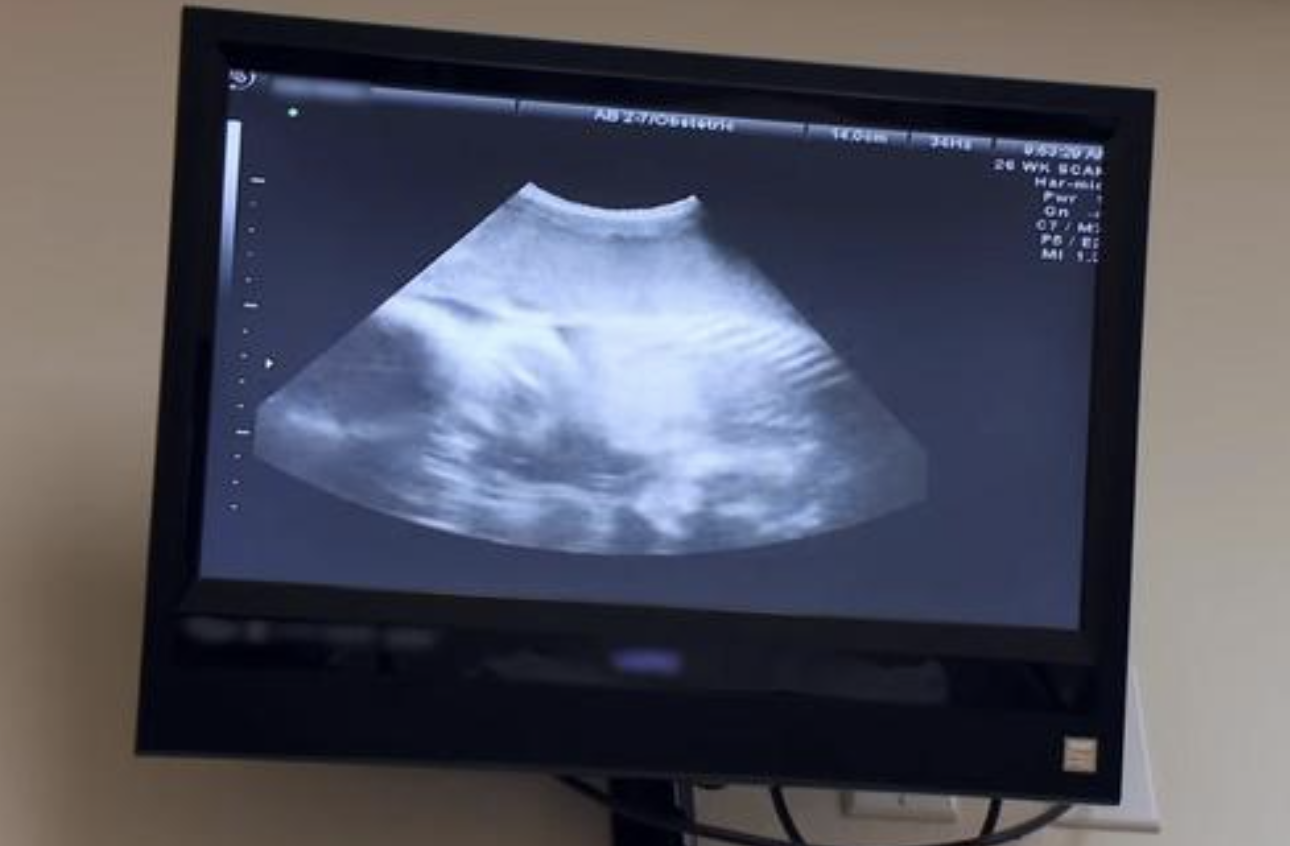

Learning she had a quadruplet pregnancy was also very alarming due to the dangers and high risk for complications. Katie’s obstetrician and medical specialists told her that she’d have a 50 percent chance of health risks and premature delivery with such a high risk pregnancy.

When Katie was 34 weeks pregnant, her team decided to schedule a C-section rather than continue to risk that moment’s notice for a term delivery. It took 20 medical professionals, but Katie safely delivered her quadruplets – Charlie, Claire, Henry & Dillon – without complication.